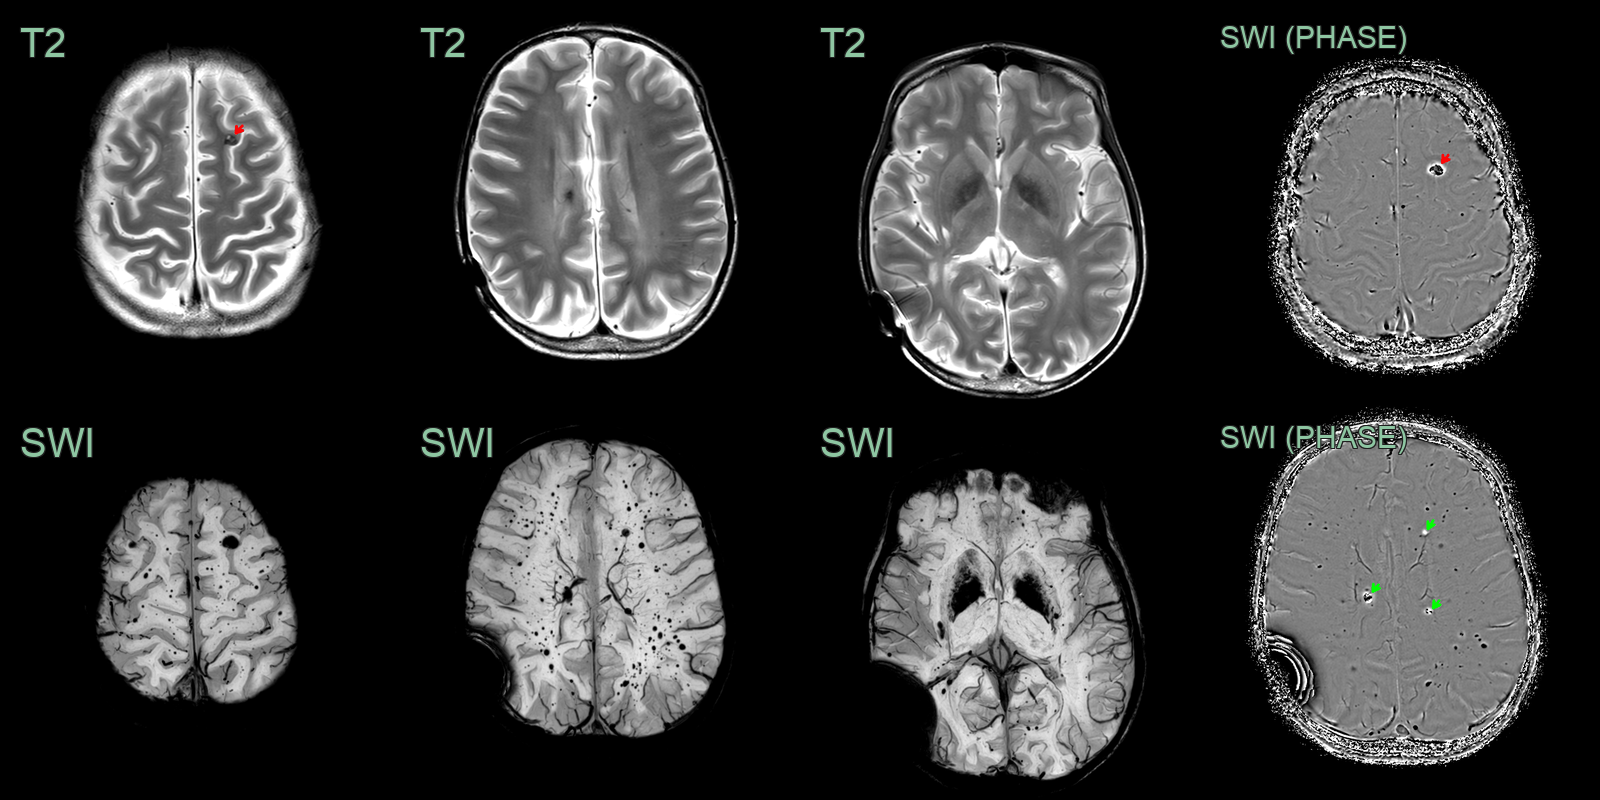

- A 25-year-old patient was treated with whole brain and spine radiotherapy due to a disseminated medulloblastoma.

- An MRI performed 10 years after treatment, showed extensive radiation induced changes including hazy white matter hyperintensity, multiple cavernomas (red arrow), microhemorrhages and excessive mineralisation in the basal ganglia.

- The phase data from SWI showed mixed paramagnetic hemosiderin (black) and diamagnetic calcium (white).